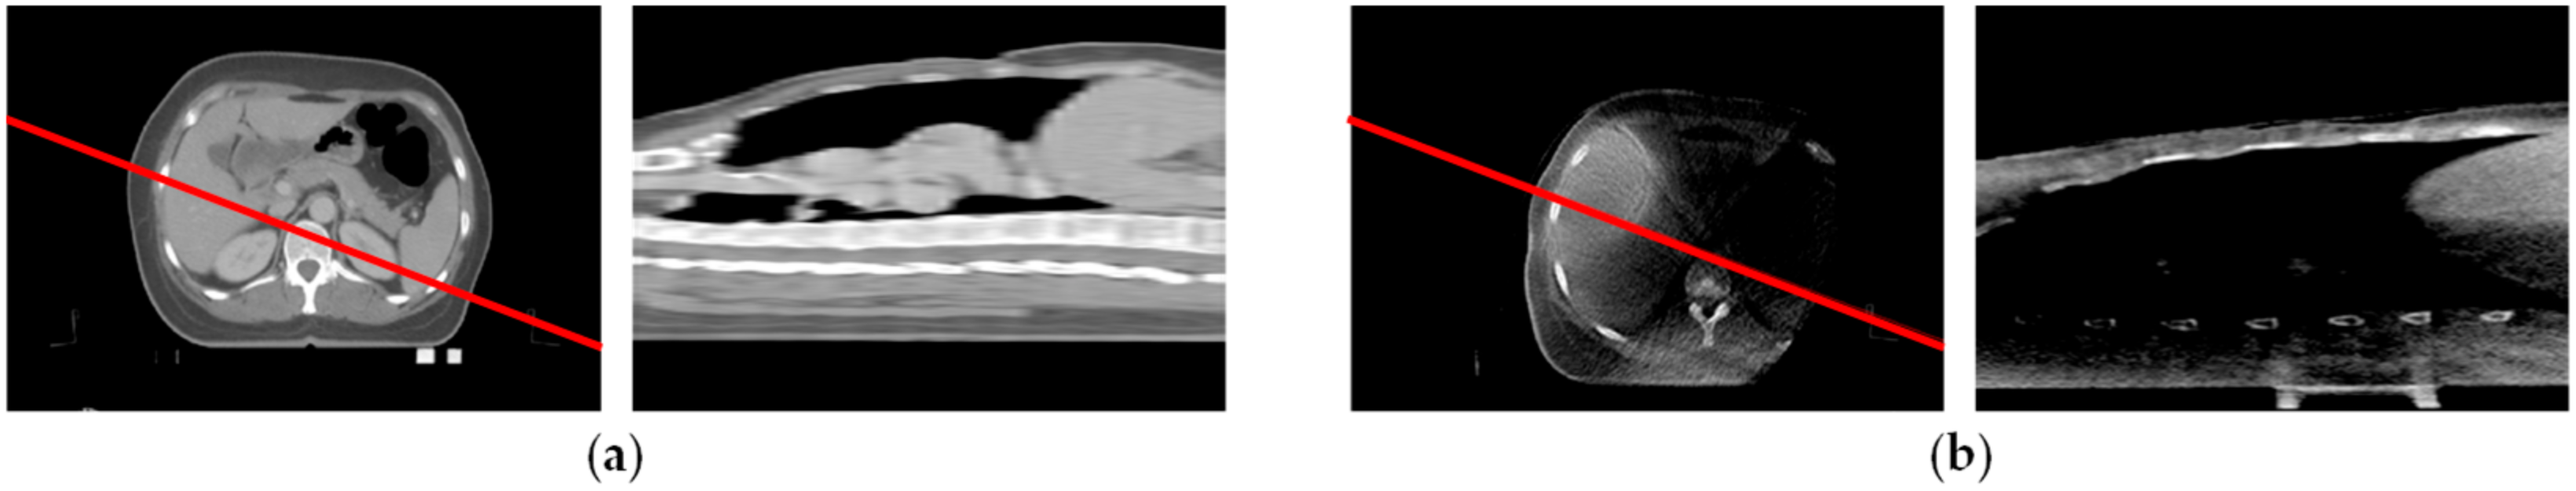

| Low Clarity | Incomplete Projection | |||

| Data set a | Data set b | Data set c | Data set d | |

| CT sequence | ![]() | ![]() | ![]() | ![]() |

| #204 | #42 | #56 | #350 | |

| CBCT sequence | ![]() | ![]() | ![]() | ![]() |

| #225 | #160 | #184 | #264 | |